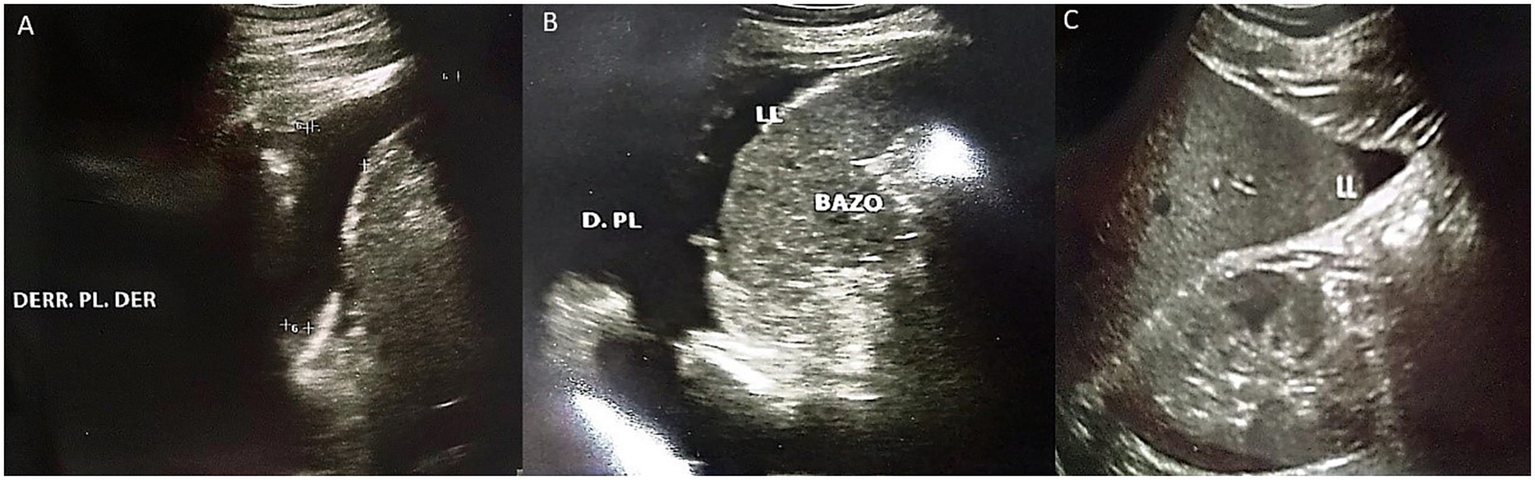

Figure 4

Abdominal ultrasound performed on the third day of hospitalization. (A) Presence of right pleural effusion is evident. (B) Presence of left pleural effusion is evident, as well as free fluid bordering the spleen. (C) Presence of free fluid bordering the liver.

On the second day of hospitalization, the patient progressively developed elevated blood pressure, an icteric tint, and abdominal distension. Complementary studies revealed thrombocytopenia, prolonged coagulation times, severe anemia, and increased nitrogen levels, requiring transfusions of blood products (fresh frozen plasma, red blood cell concentrate, and platelets). Tests for dengue and hematogenous organisms were negative (Table 1). A follow-up abdominal ultrasound on the third day revealed bilateral pleural effusion and ascites (Figure 4). At the sixth day the ECG continued to show persistent sinus bradycardia (Figure 3B).